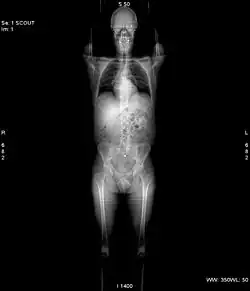

X-ray computed tomography operates by using an X-ray generator that rotates around the object; X-ray detectors are positioned on the opposite side of the circle from the X-ray source.

In conventional CT machines, an X-ray tube and detector are physically rotated behind a circular shroud (see the image above right). An alternative, short lived design, known as electron beam tomography (EBT), used electromagnetic deflection of an electron beam within a very large conical X-ray tube and a stationary array of detectors to achieve very high temporal resolution, for imaging of rapidly moving structures, for example the coronary arteries. Systems with a very large number of detector rows, such that the z-axis coverage is comparable to the xy-axis coverage are often termed cone beam CT, due to the shape of the X-ray beam (strictly, the beam is pyramidal in shape, rather than conical). Cone-beam CT is commonly found in medical fluoroscopy equipment; by rotating the fluoroscope around the patient, a geometry similar to CT can be obtained, and by treating the 2D X-ray detector in a manner similar to a CT detector with a massive number of rows, it is possible to reconstruct a 3D volume from a single rotation using suitable software.